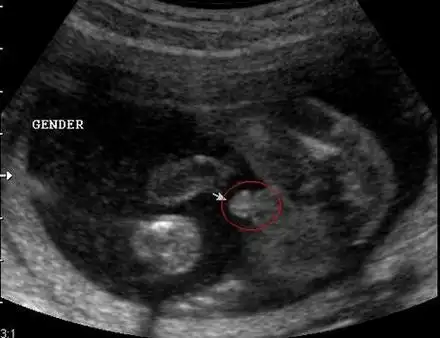

男胎儿小鸡b超显示图超准的b超图看生男生女